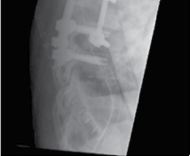

Clinical & Radiographic Imaging Archive